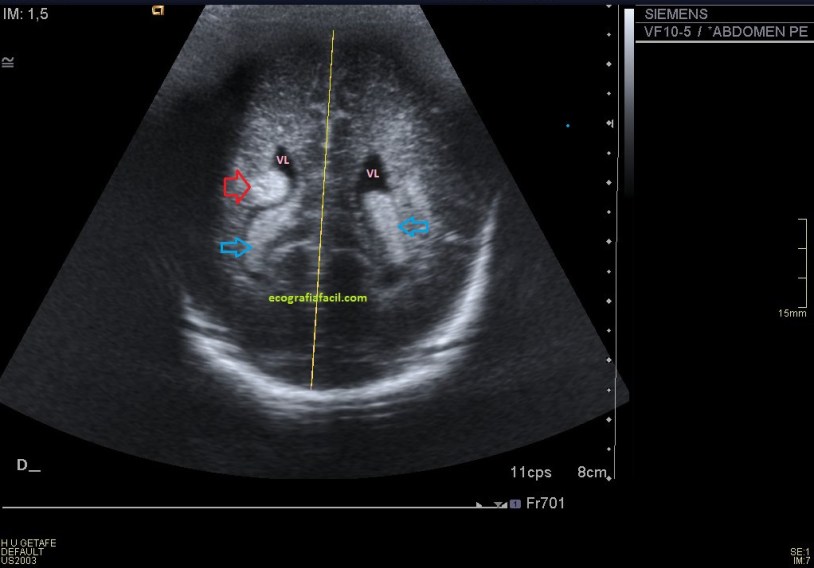

Después aplicamos el doppler, tanto el color como el modo angio donde observamos la vascularización del tumor, ojo a la escala que usemos, tiene que estar adaptada a la vascularización de la ecoestructura que estemos estudiando para ver la correctamente, de nada me sirve poner el doppler si la escala no está bien ajustada ,es decir, demasiado alta o baja, de ese modo, las lecturas de flujos lentos o rápidos no serán estudiadas por mala técnica.

Si observas en el margen superior izquierdo de la imagen 3 y la imagen 4 vas a ver que la escala es baja (3,8 cm/sg), por tanto el flujo de la lesión sabemos que es baja. Si nosotros usamos una escala muy alta, no podríamos ver las imágenes que estás viendo, y como en esta imagen, en todas las imágenes de neoformaciones a las que te enfrentes en tu día a día.